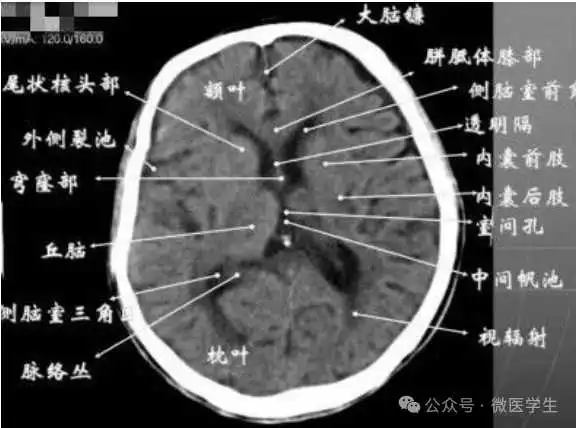

由额、颞、枕叶构成,两侧侧脑室体部之间为透明隔,外侧为尾状核和体部。侧脑室后角(枕角)可不对称,室内可见脉络丛钙化。中线处可见大脑纵裂池和大脑镰。

内侧壁侧脑室体部被胼胝体分开,侧脑室体部的外方为顶叶,顶枕沟及中央沟将大脑为为额、顶、枕叶。